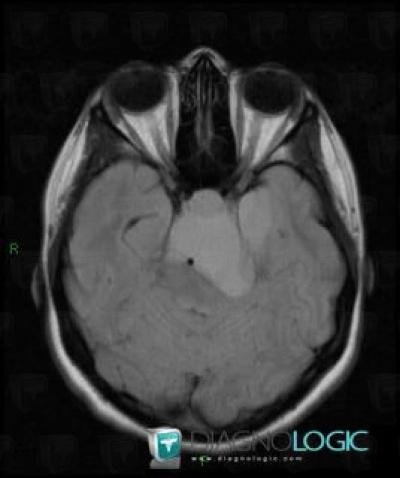

Craniopharyngiome, Hypophyse et région parasellaire, IRM

Voici les informations spécifiques à l'image clé ci dessus:

- Diagnostic Craniopharyngiome, Localisation(s) Hypophyse et région parasellaire, comportant les gammes Lésion en hypersignal T2 sellaire ou parasellaire